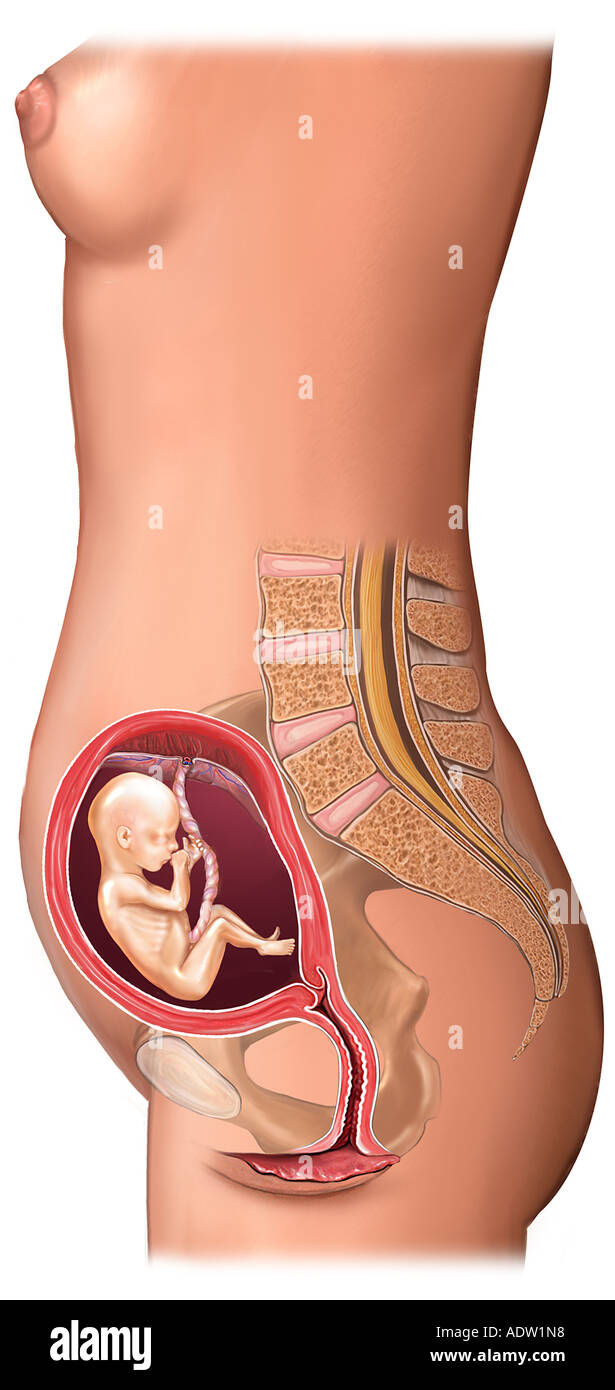

Расположение плода на 15-й неделе беременности: фотографии и иллюстрации